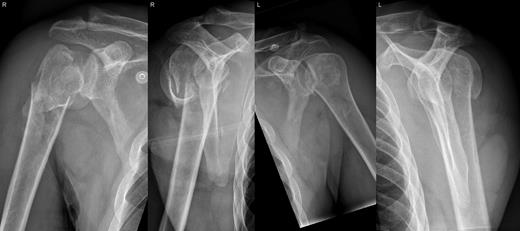

A 48-year-old patient was referred to a level I trauma center after the first incidence of an epileptic convulsion. The patient was alert and oriented with retrograde amnesia from the time of convulsion. Peripheral neurology was normal. The X-rays showed bilateral posterior shoulder dislocation with fractures of both humeral heads (Fig. 1). A CT of the head and both shoulders was performed to exclude intracerebral pathology and to achieve better demonstration of the shoulder fractures (Fig. 2). According to the AO fracture classification, he had a 11-C3.1 fracture on the left side and a 11-C3.3 fracture on the right side. The right side fracture was treated with a cementless hemiarthroplasty (OrTra®, Zimmer, Germany), while an open reduction and internal fixation (ORIF) with an angular stable plate (Philos®, Synthes, Germany) was performed on the left. Despite the high incidence for humeral head necrosis after ORIF in this fracture type, this option was chosen based on the young age of the patient. Postoperative X-rays and CT showed adequate positions of the implants (Fig. 3). The shoulders were immobilized in Gilchrist bandages followed by passive mobilization for the first 6 weeks by physiotherapy with a limitation for abduction and anteversion to 90°. There were no complications intraoperatively or in the first postoperative time. Patient was discharged after 8 days. Antiepileptic therapy was initiated with 5 mg clobazam and subsequent increasing doses over the following weeks. There were no more signs of epilepsy in the follow-up. A CT 4 months after operation showed dislocation of a fragment on the left side which was subsequently resected. At the 1-year postoperative review, the patient showed impingement of the left shoulder with abduction limited to 50° by both the plate and an osteophyte. Radiological assessment revealed signs of necrosis of the head. The plate was removed and the osteophyte resected. Eighteen months after injury, the left shoulder showed progressive avascular osetonecrosis of the head (Fig. 4) and after plate removal an inversed prosthetic replacement had to be performed (Fig. 5). At the last follow-up 3 years after injury, the patient was free of pain with a bilateral range of motion of 90° abduction and elevation.

Avascular head necrosis over the following one and a half years on the left side with ongoing necrosis after plate removal.